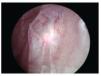

El sexto caso presentado, se trata de paciente masculino con antecedente de tabaquismo intenso de larga evolución, con índice tabáquico de 20, así como diabetes mellitus tipo 2 e insuficiencia renal crónica terminal, ambas de tres años de diagnóstico, sometido a manejo médico. Quien cursaba con una evolución aproximada de un mes de hematuria macroscópica, total, silente, con coágulos amorfos, la cual se acompañaba de pérdida ponderal de aproximadamente 5 Kg. Fue valorado mediante USG y uretrocistoscopía, encontrándose lesión tumoral de aspecto arboriforme, localizadas en cara lateral derecha y en región retrotrigonal, las cuales se resecan en el año 2010 mediante ablación. Se hizo diagnóstico histopatológico de carcinoma urotelial de bajo grado T1a, sin invasión muscular ni afección ganglionar, siendo manejado con inmunoterapia mediante BCG por seis semanas y luego mensual durante seis meses, cursando en primeras dos cistoscopias de control a los tres y seis meses, sin actividad tumoral. Sin embargo, a los nueve meses se realizó nueva cistoscopía encontrándose lesión papilar arboriforme en pared lateral izquierda, por lo cual fue llevado a resonancia magnética (Figuras 9 y 10), sin evidencia de compromiso de la muscular ni extra-vesical, por lo que se realiza ablación con laser Holmium, empleando una energía total de 12.8W (Figuras 11 y 12), logrando la ablación total de las mismas.

Figura 10. Cistoscopia de control, un año posterior a ablación de tumor vesical en donde se observa lesión en pared vesical izquierda, de aproximadamente 4 cm de longitud.

Figura 11.Resección de tumor vesical mediante laser Holmium, se observa incisión inicial.

Figura 12.Resección de tumor vesical, se observa base del sitio de resección.